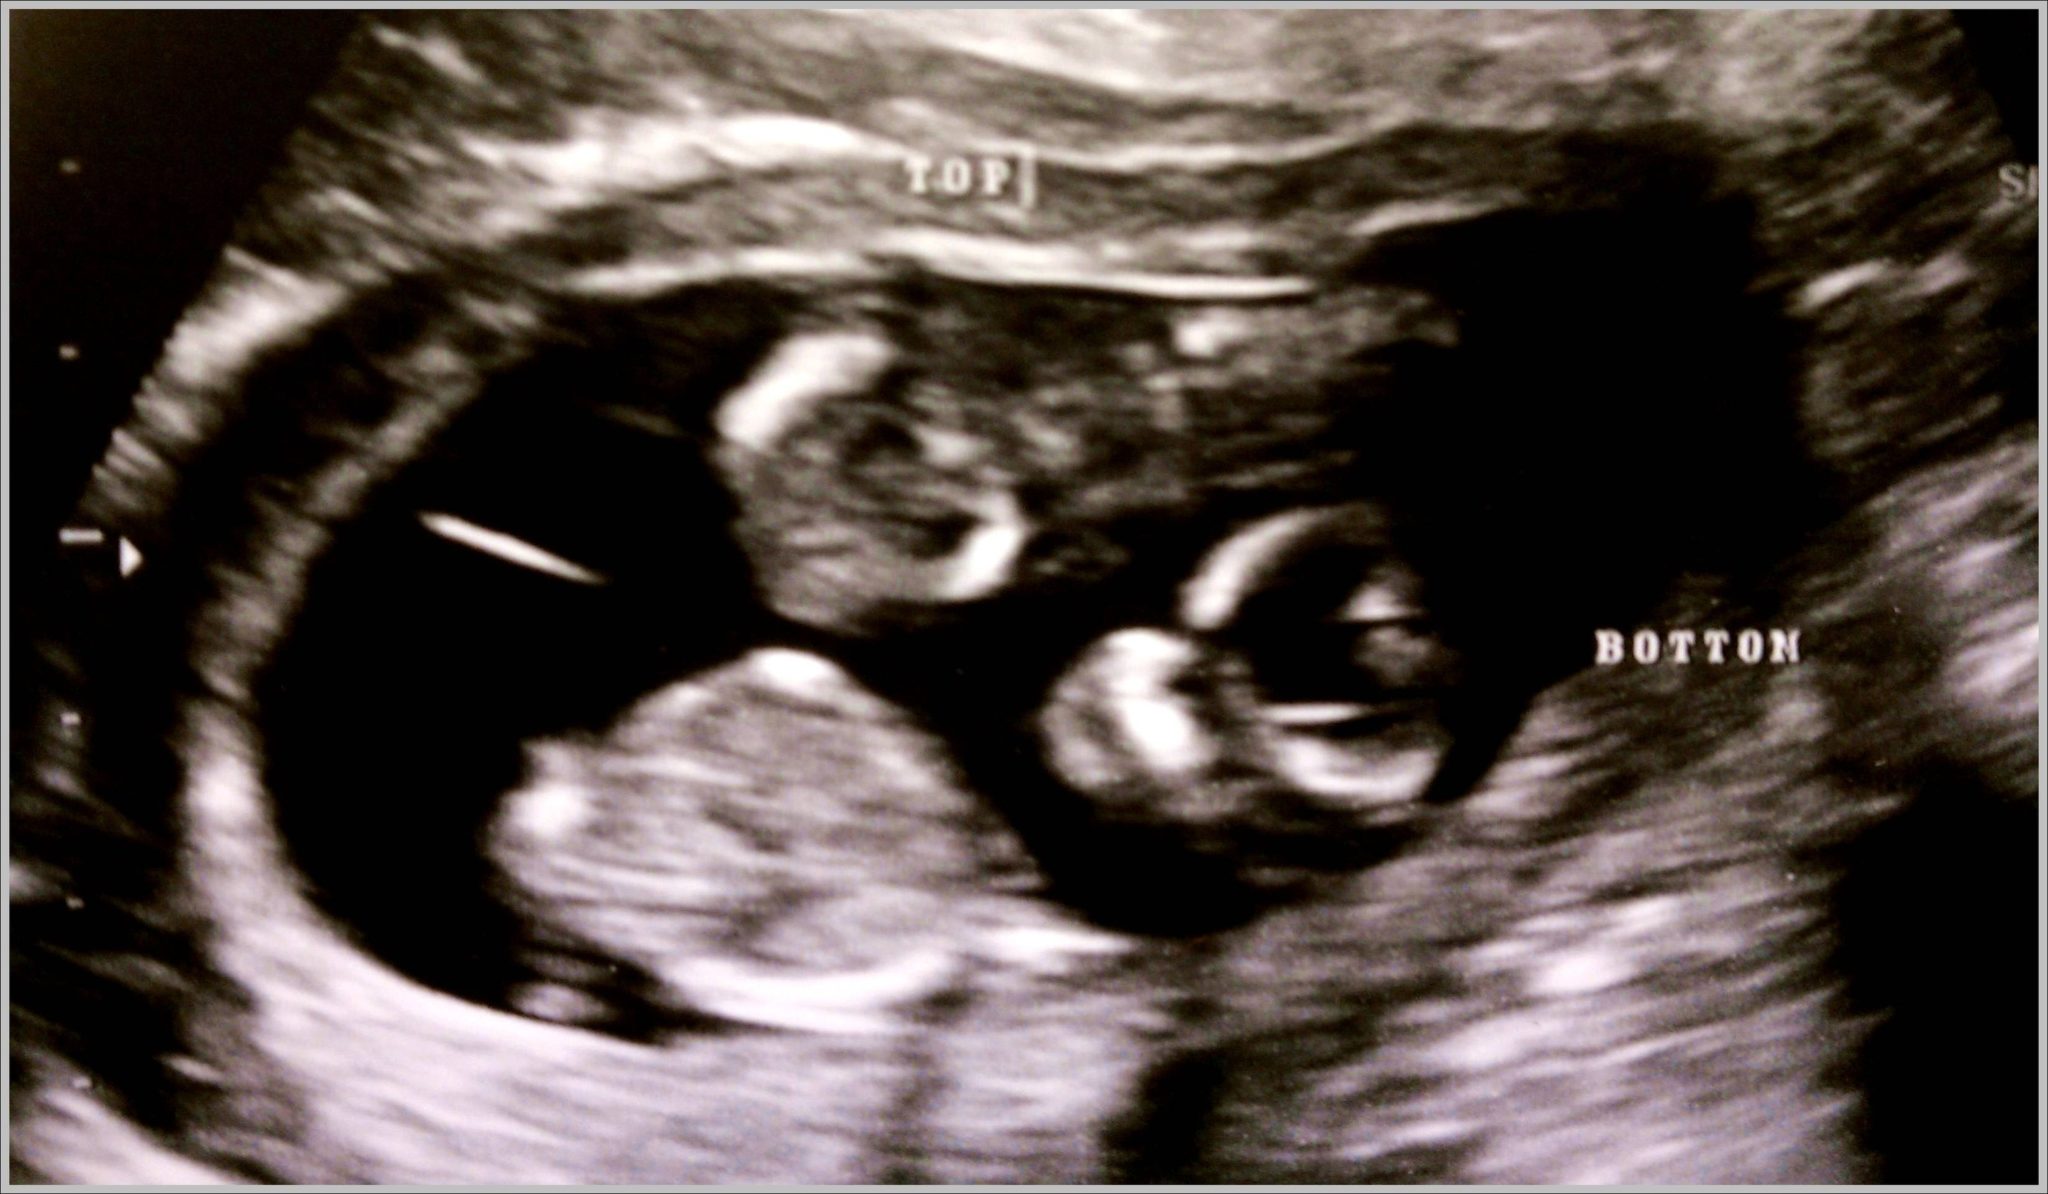

What Does An Identical Twin Ultrasound Look Like . Often, doctors will be able to determine the likelihood of twins being fraternal or identical based on whether they share a placenta. At this early stage, the signs of a twin pregnancy might include the presence of two distinct gestational sacs or yolk sacs. At this stage, the presence of two yolk sacs can be seen, and separate heartbeats distinguished. What do identical twins look like at 8 weeks? How to tell if twins are identical or fraternal from an ultrasound? The exact time twins can be detected depends on the type of twins, for example, if they’re identical (from one egg) or not. Twins who share a placenta are. An ultrasound with twins will show the babies as two dark spots in the uterus. Ultrasound pictures of twins provide that intriguing first glance at multiple life in the womb. At 8 weeks of pregnancy, identical twins will appear as two separate embryos within the womb. Check out hundreds of amazing twin ultrasound images!